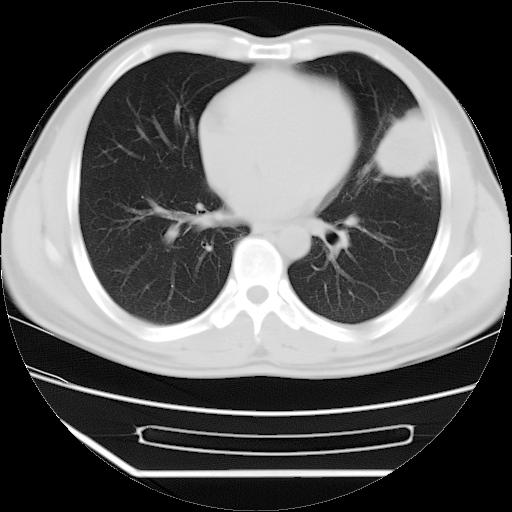

男,38岁,于2009年8月9日晚突发左侧胸痛,今x线提示左下肺阴影,为了明显确诊断,行ct检查,

血常规:嗜酸性细胞增高,单核细胞增高。

病灶发生在下叶,密度均匀,边缘模糊、毛糙,周围血管纹理增强扭曲改变,靠近胸膜处病灶胸膜反应明显。

支持考虑---球形肺炎。

左肺舌叶病变。主体病灶呈类圆形中心密度低,成液化趋势周边班片影分布

考虑肺脓肿

虽然实验室检查支持炎性病变,且病变内有坏死改变(中央呈大片状低密度影),但仍不能掉以轻心,鳞癌也可以有这种影像改变。